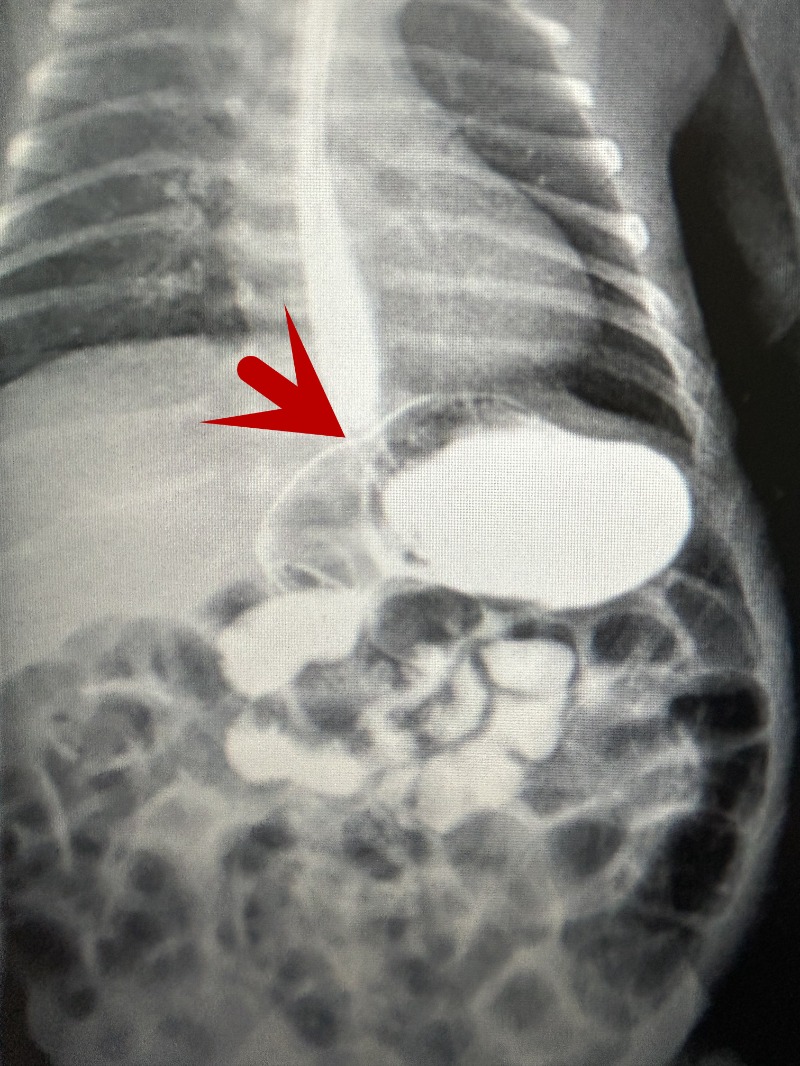

为寻找原因,新生儿科和医学影像科联系,做好充分准备,为孩子进行了上消化道造影的检查,这也是目前医院给最小的体重患儿进行该项检查,最终明确患儿为新生儿胃扭转。

新生儿科许存欣主任介绍,一些研究表明,新生儿胃扭转发生率为0.25‰,常误诊为喂养不耐受或者其他疾病,且一些早产儿或病重者不便移动,不能及时行上消化道造影,导致诊治延误。